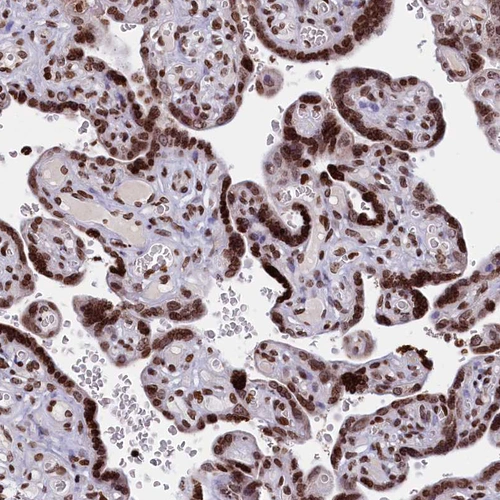

Immunohistochemical staining of human cerebral cortex shows strong nuclear positivity in glial cells.